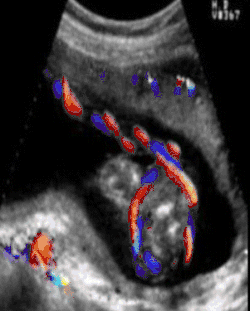

Doppler ultrasound showing a nuchal cord

A study published in 2004 was done to establish the sensitivity of ultrasound in the diagnosis of a nuchal cord. Each of 289 women, induced the same day, underwent a transabdominal ultrasound scan with an Aloka 1700 ultrasound machine with a 3.5 MHz abdominal probe, using gray-scale and color Doppler imaging immediately prior to induction of labor. Presence of the cord was sought in the transverse and sagittal plane of the neck. A nuchal cord was diagnosed if the cord was visualized lying around at least 3 of the 4 sides of the neck. A cord was actually present at delivery in 52 of the 289 women. Only 18 of the 52 cords or 35% of the nuchal cords were detected on ultrasound done immediately before delivery, and 65% of nuchal cords were not detected. Of the 237 cases where there was no cord at delivery, ultrasound had false positive results, i.e. diagnosed a cord in 44 of the 237 cases (19%) in which there was no cord present at all. In this study, ultrasound was only 35% accurate at finding a single loop, and only 60% accurate at detecting a nuchal cord wrapped multiple times around the neck.[9]

In no study was it possible by ultrasound to distinguish between a loose or a tight cord, although at least 3 attempted to do so. Peregrine[9] concludes that ultrasound diagnosis of nuchal cords will only be useful if doctors are able to do so reliably and predict which of those fetuses are likely to have a problem. However, perinatologists routinely look for umbilical cord issues in monoamniotic twins. Studies have shown an improvement in outcomes where cord entanglement was prenatally identified in these cases. Ultrasound measurement of the velocity of flow in the cord may be useful in the management of twins and chronically growth-retarded fetuses. Of course this depends on the training of the sonographer. To date there are no ultrasound courses which teach the identification of nuchal cord to physicians or technicians. A recent review by Wilson of the American Academy of Ultrasonography Technicians recommends the documentation of umbilical cord issues.[10]